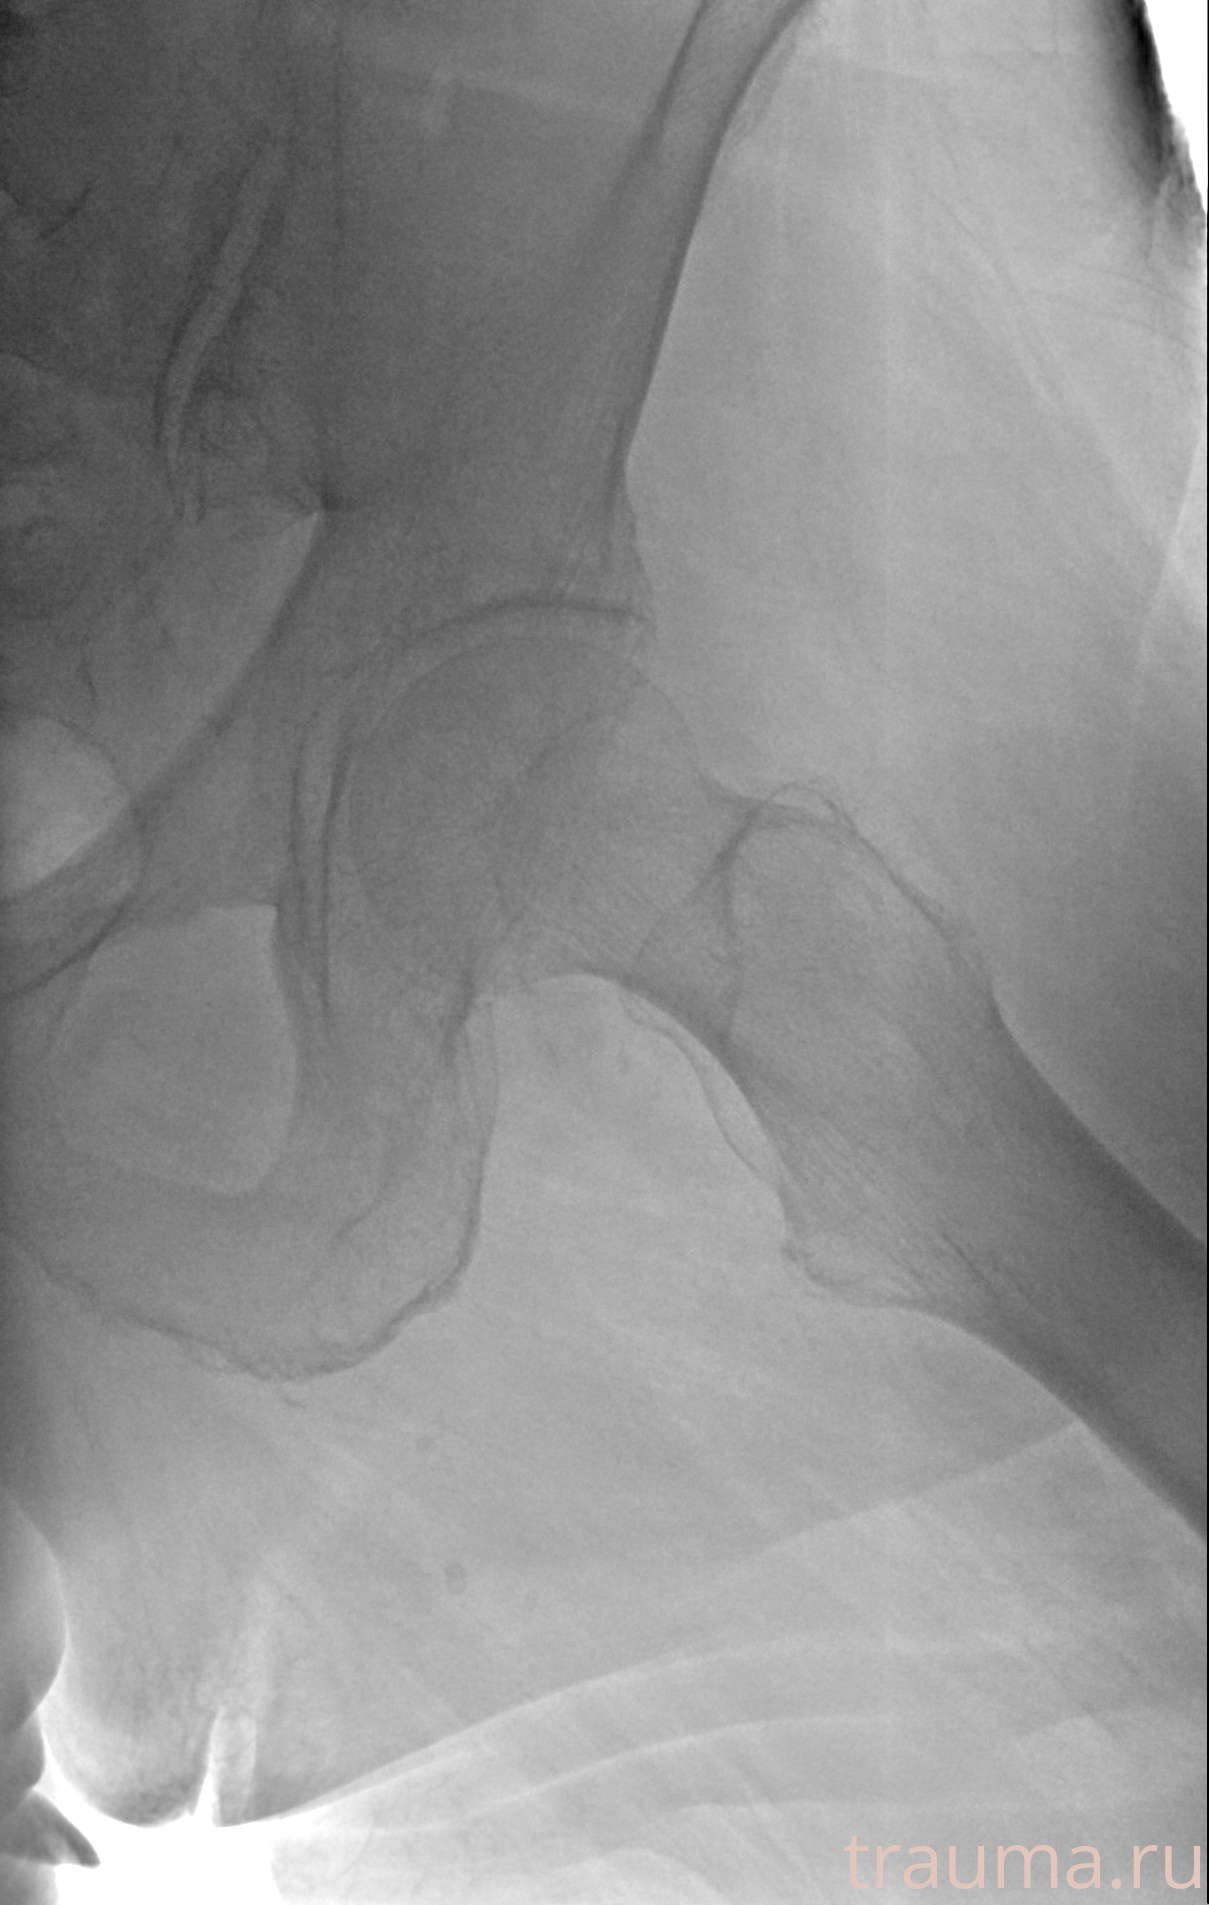

Рентгенограммы

Рентген на дому: по вашему адресу приезжает врач-рентгенолог, травматолог-ортопед с мобильным рентгеновским аппаратом, проводит диагностику травмы или заболевания, делает необходимые рентгенограммы, дает рекомендации по дальнейшему лечению. Получить качественные снимки в домашних условиях возможно благодаря уникальной методике, разработанной МосРентген Центром для института  Склифосовского